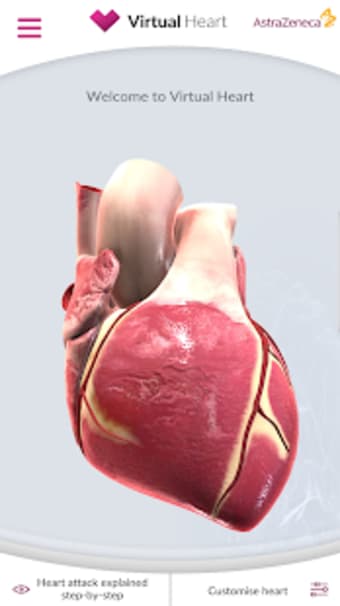

Virtual Heart - ANZ är en gratis programvara för Android, som ingår i kategorin 'Medical'.Om Virtual Heart - ANZ för Android

Virtual Heart - ANZ är tillgänglig för Android 9.0 eller högre. Den nuvarande versionen av programmet är 2.2, och du kan köra den endast på engelska.